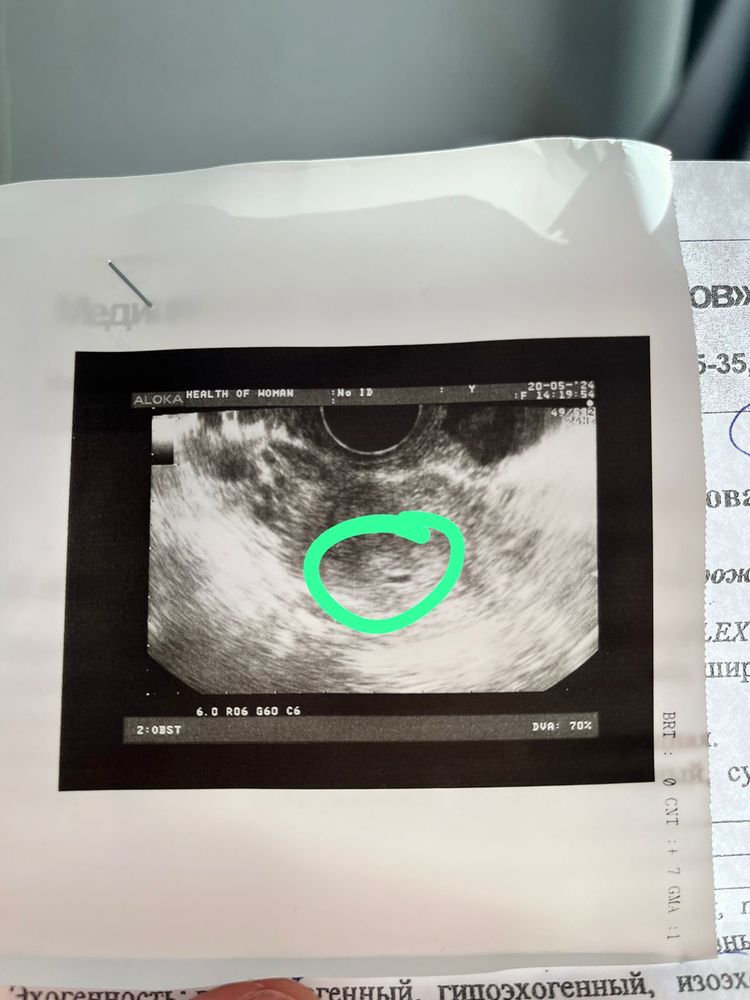

Помните,я тут писала ,что до овуляции нашли что то в матке в июне,типо кругляшка(фото прикреплю,отметила зеленым )Так и не поняла,что это было…После месячных уже его не было.В

Возможно что это типо полипа,миомы??